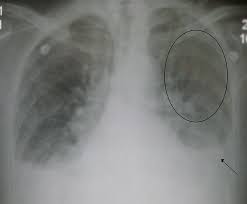

Peripartum Cardiomyopathy The Bmj

Peripartum Cardiomyopathy The Bmj from www.bmj.com

Peripartum Cardiomyopathy Circulation

Peripartum Cardiomyopathy Circulation from www.ahajournals.org